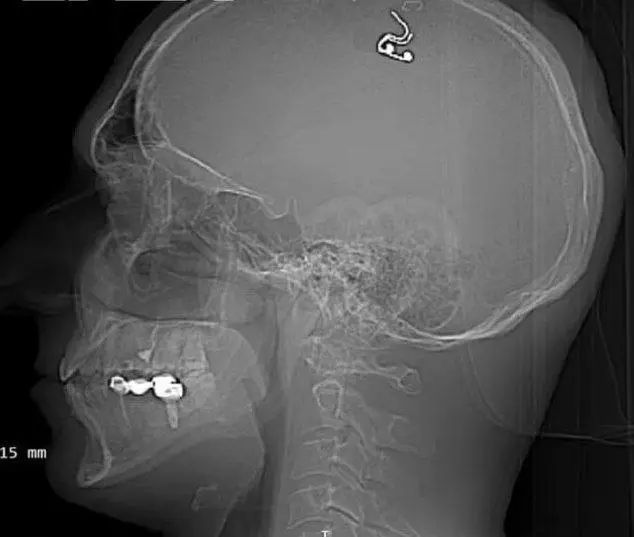

СМИ сообщают, что 40-летний Михаил Радуга самостоятельно прооперировал себя дома в Алматы, где он недавно стал проживать. Перед этим он тщательно готовился: долгое время изучал ролики на «Ютубе» о работе нейрохирургов и даже тренировался на пяти овцах. Спустя время мужчина купил дрель в хозяйственном магазине и просверлил себе голову, фиксируя кожу скрепками, а затем вживил в мозг электрод. Россиянин отметил, во время своего эксперимента он едва выжил после операции, потеряв примерно литр крови из-за своей неопытности.

Радуга полагает, что инородное тело, стимулируя моторную кору мозга, позволит ему управлять снами. Как оказалось, россиянин давно изучал эту жуткую тему, а шесть месяцев назад для установки чипа он даже собирался обратиться к врачам, однако из-за «уголовных рисков и других известных событий» пришлось отказаться от затеи. Но останавливаться Миша не стал и решил, что собственными руками сможет «расширить представление о возможностях человека».

О произошедшем узнал консультант-нейрохирург из Оксфордского университета Алекс Грин. Специалист считает, что мужчина запросто мог умереть или получить инсульт, а после операции ему может грозить развитие эпилепсии. Стоит отметить, что пока непонятно, стал ли россиянин управлять сновидениями или нет.